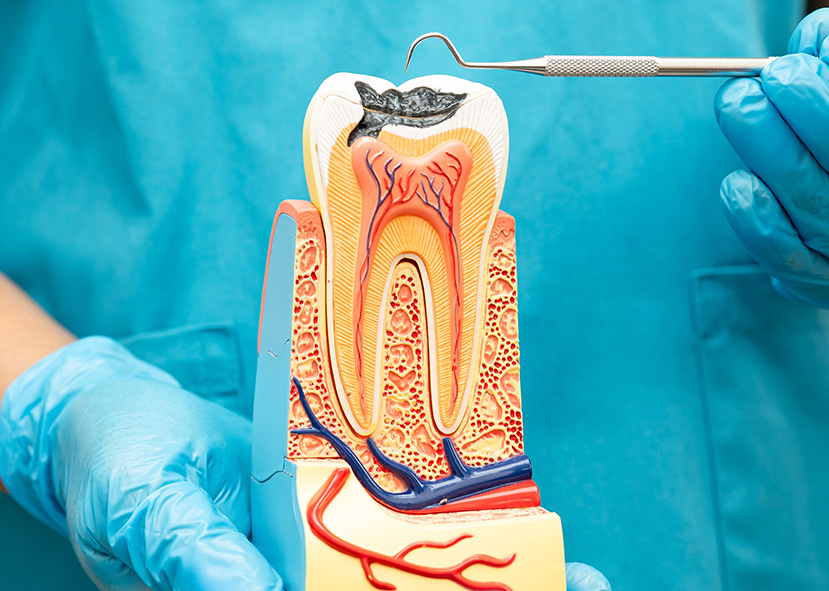

Root Canal Treatment to Save Your Tooth

Gentle, effective relief from tooth pain and infection—while preserving your natural tooth.

A root canal may sound intimidating, but it’s actually a straightforward, highly effective way to save a tooth that’s infected or severely decayed. At Crown Dental Group, our experienced team uses modern techniques and gentle care to ensure your root canal treatment is as comfortable as possible—with long-lasting results.

While extraction removes the tooth entirely, root canal therapy saves the tooth by removing the infected pulp and sealing it—preserving your bite and appearance.